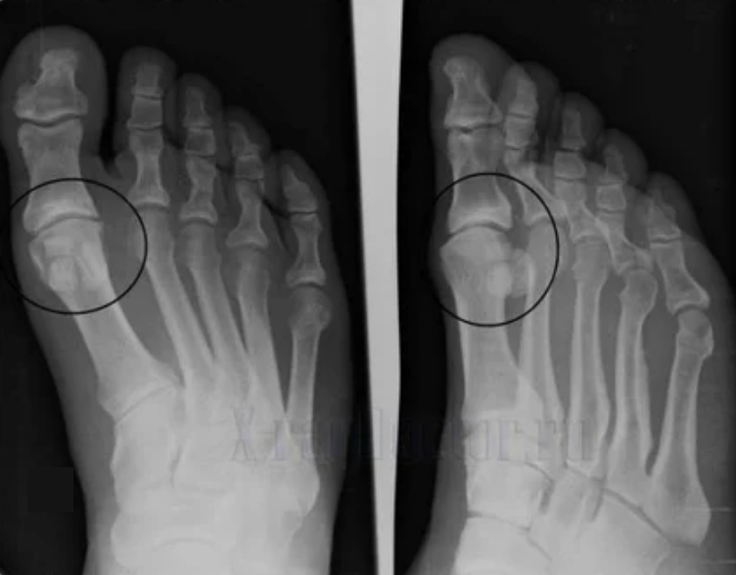

To make a diagnosis, rheumatologists study the patient's complaints and prescribe an X -ray examination.Most often, radiography is used in 2 projections.The doctor looks at the presence of dystrophic disorders in hyaline cartilage and bone joints.If the articular gap is reduced, the bones are deformed or flattened, there are cystic formations on the surface of the cartilage, osteophytes are obvious signs of arthrosis.During the inspection, arthrosis indicates the instability of the joint: the axis of the limbs and subluxation is disturbed.

Often an X -ray picture is not able to give complete information about the condition of the joint.For a more thorough study, computed tomography is prescribed, it is effective for examining bones.MRI is more often used to study soft tissues.